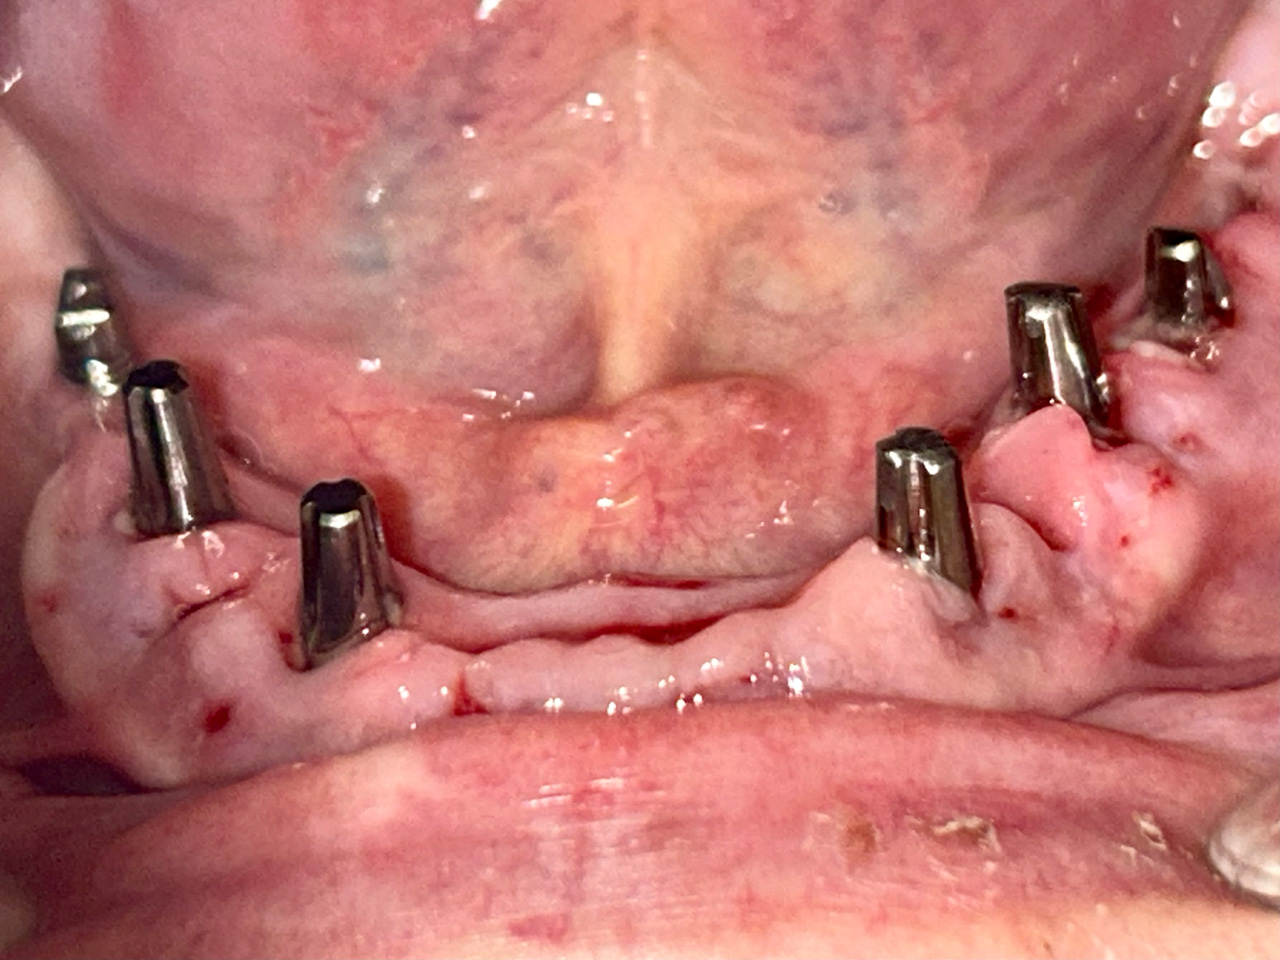

Alsó állcsont teljes rehabilitációja 72 óra alatt

Alsó állcsont teljes rehabilitációja 72 óra alatt, azonnal terhelhető implantátumokkal súlyos paradontitisben szenvedő dohányzó páciens esetében. Az alsó állcsont fogai mind mozogtak az előrehaladott fogágypusztulás miatt.

A fogakat eltávolítottuk, a gyulladt, fertőzött csontot kitakarítottuk, kifertőtlenítettük, majd azonnal implantáltunk.

Svájci, IHDE márkájú, azonnal terhelhető implantátumokat helyzetünk be, és ezekre harmadnapra rögzített, hosszútávú, fémvázas, esztétikus műanyaggal leplezett hidat ragasztottunk be.

Ezt az ideiglenes hidat a sebek gyógyulása miatt használjuk, de tartóssága miatt véglegesként is használható. A legtöbb esetben, ahogy itt is, 6 hónap múlva porcelán hídra cseréljük, a teljes gyógyulás után.